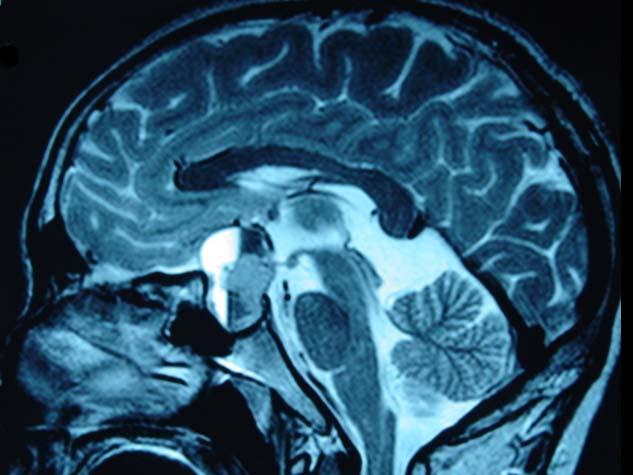

问题 男,47岁,头痛3年余,最近2个月感觉视力下降,MRI检查如图,最可能的诊断为()

选项 A.垂体瘤 B.颅咽管瘤 C.垂体囊肿 D.垂体腺瘤囊变 E.脑膜瘤

答案 D